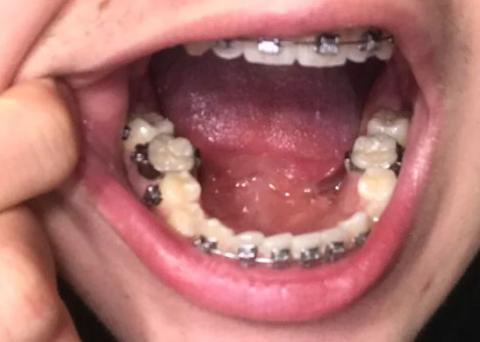

Dental Case Analysis: Lower Arch With Braces and Multiple Carious Lesions

The image shows the lower dental arch with fixed orthodontic brackets in place. Several posterior teeth exhibit dark cavitated areas, consistent with active dental caries. Oral hygiene challenges are evident around brackets and molars.

Multiple lower molars with visible dark cavities